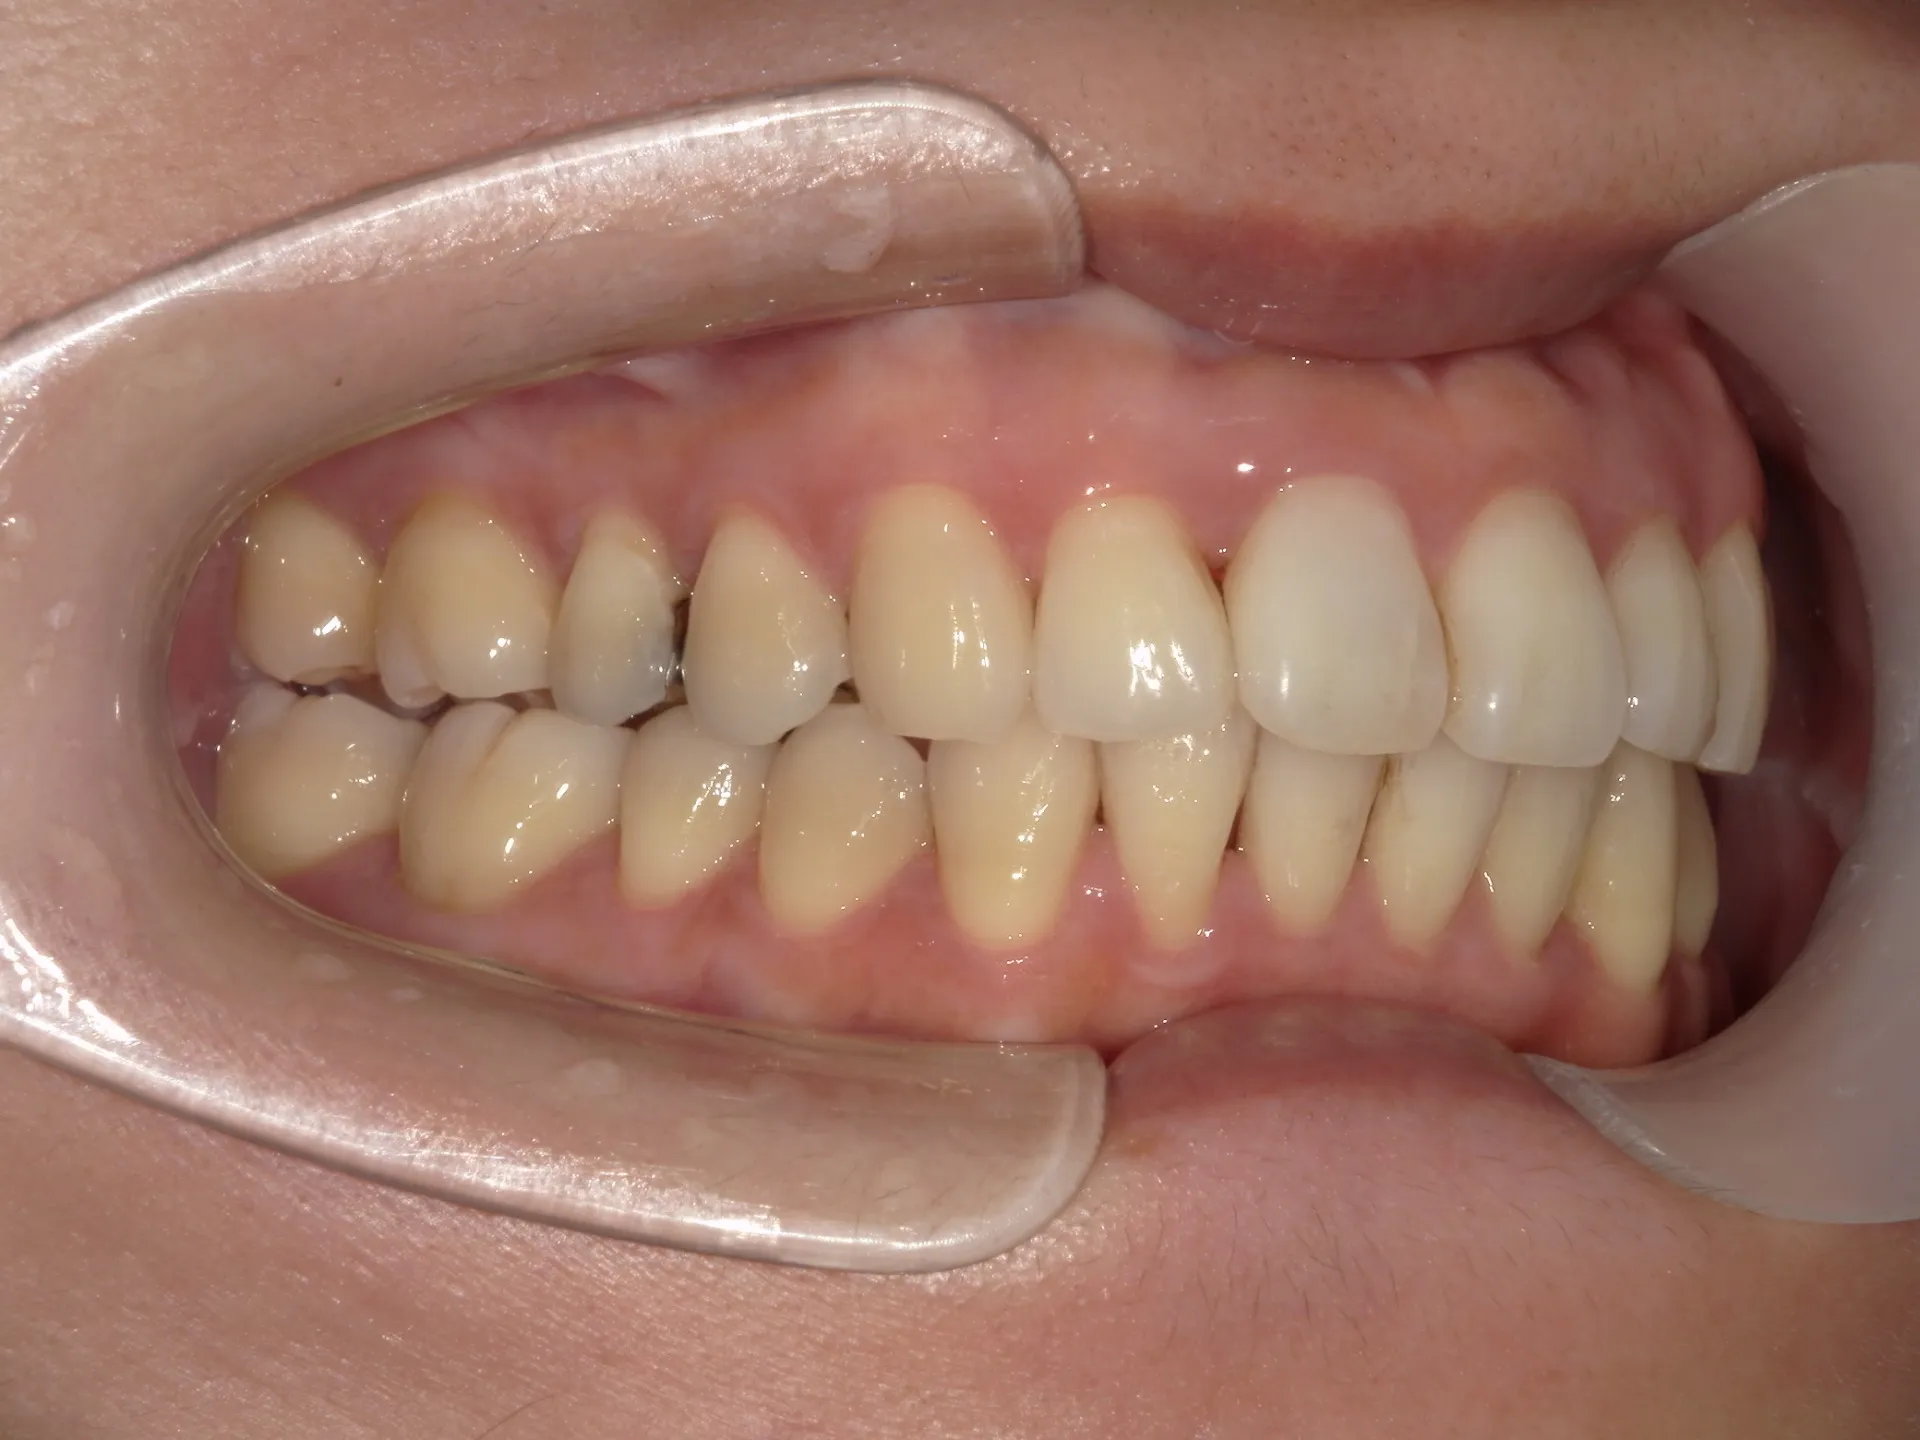

今回は矯正治療とウォーキングブリーチというホワイトニングを併用して治療した症例をご紹介いたします。

そのため今回は通常の矯正治療とその後にご自身の歯を利用してウォーキングブリーチを行いました。

セラミックの被せ一本で治せた方が、費用感や治療期間は少なくできますが、仕上がりを考えるとやはり今回のようなケースでは、矯正治療とホワイトニングを併用した方が良い選択であったと考えられます。